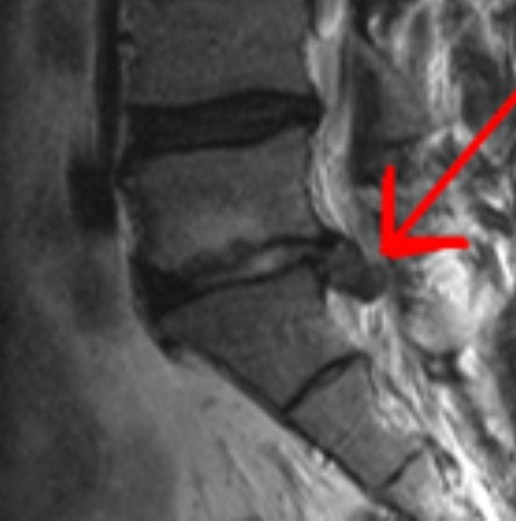

HNP (hernia del núcleo pulposo)

Dolor de espalda, radicular, ciática déficit neurológico asociado a compresión de raíz.

Dolor de espalda, radicular, ciática déficit neurológico asociado a compresión de raíz.